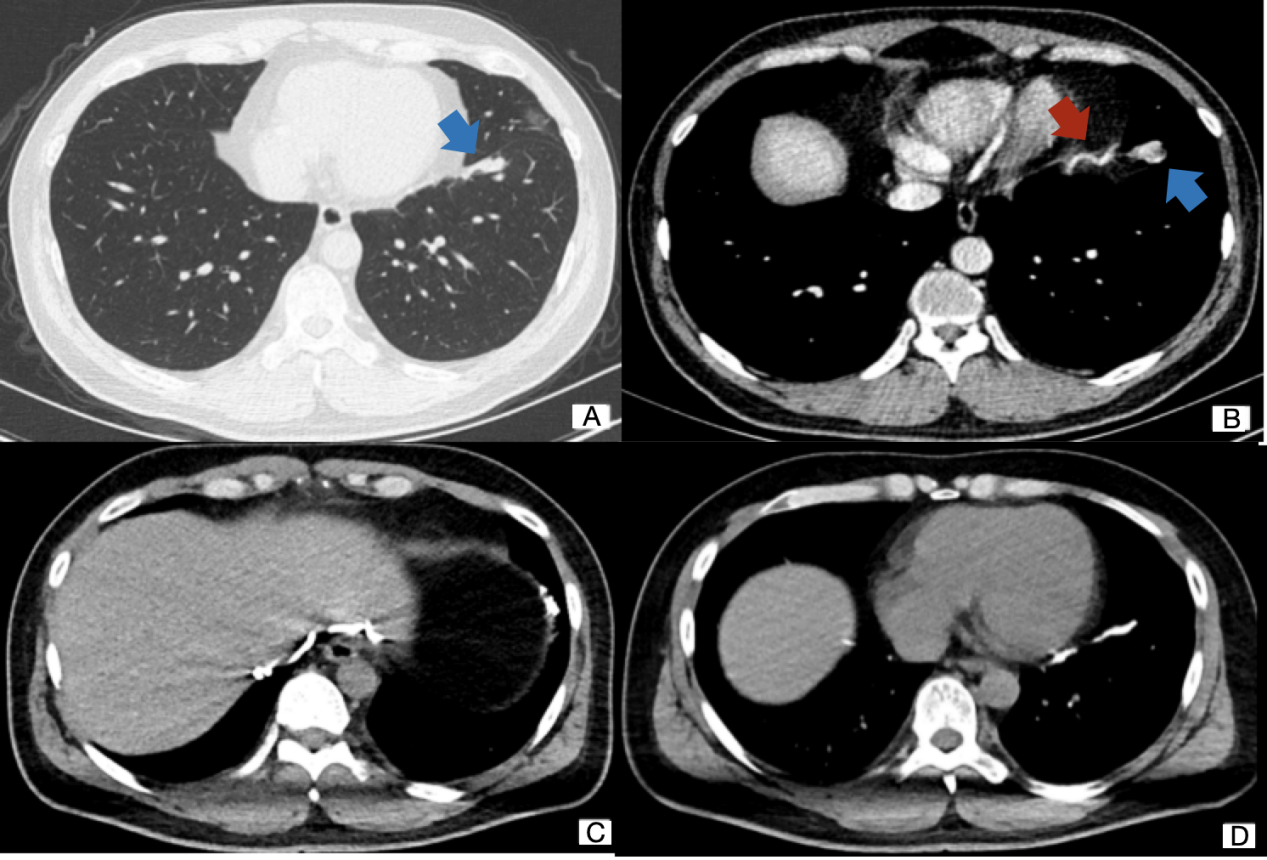

A 32-year-old man was admitted to the hospital with recurrent hemoptysis. He was previously healthy and did not have any family history of hemoptysis. He had repeated hemoptysis without obvious causes for more than a week and condition aggravation in the morning and evening, but no cough, expectoration, fever, nor dyspnea. Upon examination, there was no obvious abnormality. A preoperative nonenhanced computed tomography (CT) scan of the chest showed that a soft tissue density stripe abutting on the oblique fissure in the left lower lobe (Figure 1A). And the contrast-enhanced CT scan revealed about a 1.3 cm-sized well-enhanced vascular mass and an abnormally connection between the thickened right inferior phrenic artery and the branch of the pulmonary artery of the left lower lobe (Figure 1B). A systemic (right inferior phrenic artery)-pulmonary artery (branch of the pulmonary artery in the anteromedial basal segment of the left lower lobe) fistula was diagnosed.

The patient refused the operation and had received embolization treatment. Two days later, we started the treatment course. Prior to embolization, vascular malformation was confirmed by selective angiography. The views have tortuous and thickened right inferior phrenic artery (Figure 1 C) and malformed anastomosis at the end of left inferior pulmonary artery display (Figure 1 D) but without obvious pulmonary vein (Figure 2 A). During the diagnostic angiography, 1.5 ml of iodized oil and 0.5 ml of tissue glue embolization were performed with a Super selective microcatheter. After embolism, there was no blood flow or a little blood flow (Figure 2 B) and soon the patient's symptom disappeared. He had simple misery in operation areas the first postoperative day, and the pain gradually ease. We consider this discomfort may related to surgical trauma. Then he was discharged from hospital after four days. No vascular abnormality was visible three and one half months later when a plain and enhanced CT were done. The patient reported minimal pain when pressure to the wound but no other symptoms.

Figure 1 (A) : CT pulmonary window showed a soft tissue density strip abutting on the oblique fissure in the left lower lobe. (B) A contrast-enhanced CT scan showed a malformed vascular mass and significantly thickened right phrenic artery. (C) Selective angiography of the right inferior phrenic artery. (D) Selective angiography of the left pulmonary artery.